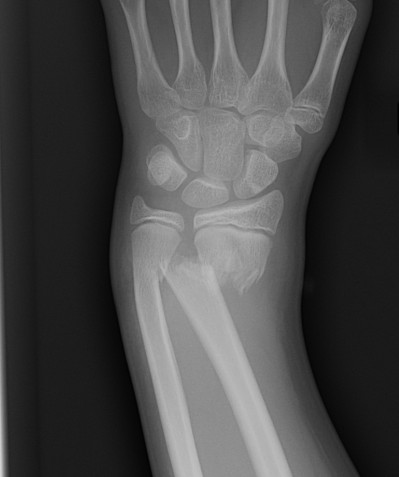

Xray

CT

MRI